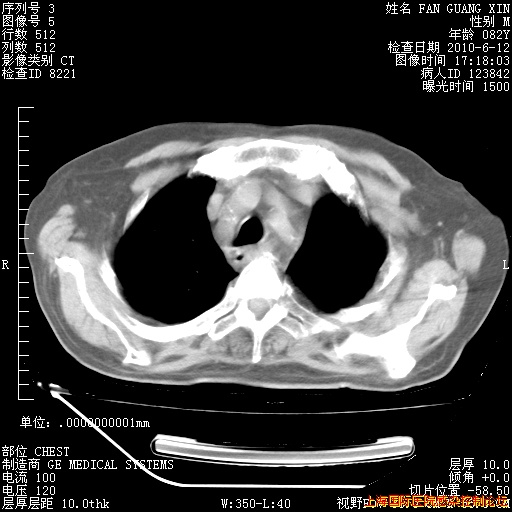

今天复查CT

今天CT

整整相隔30天的肺部CT好像有所好转啊。甲强龙减量第3天,需要观察体温。

海管,自昨日你和我通完话后,不知您岳父消化道症状有无缓解?体温怎样?阅读7.12日胸部ct,个人认为目前激素治疗是有效的,甲强龙减量是适宜的。因在抗痨治疗,需密切观察肝功、肾功能和血常规。不过,老年、长期住院和大量使用激素,很担心菌群失调发生